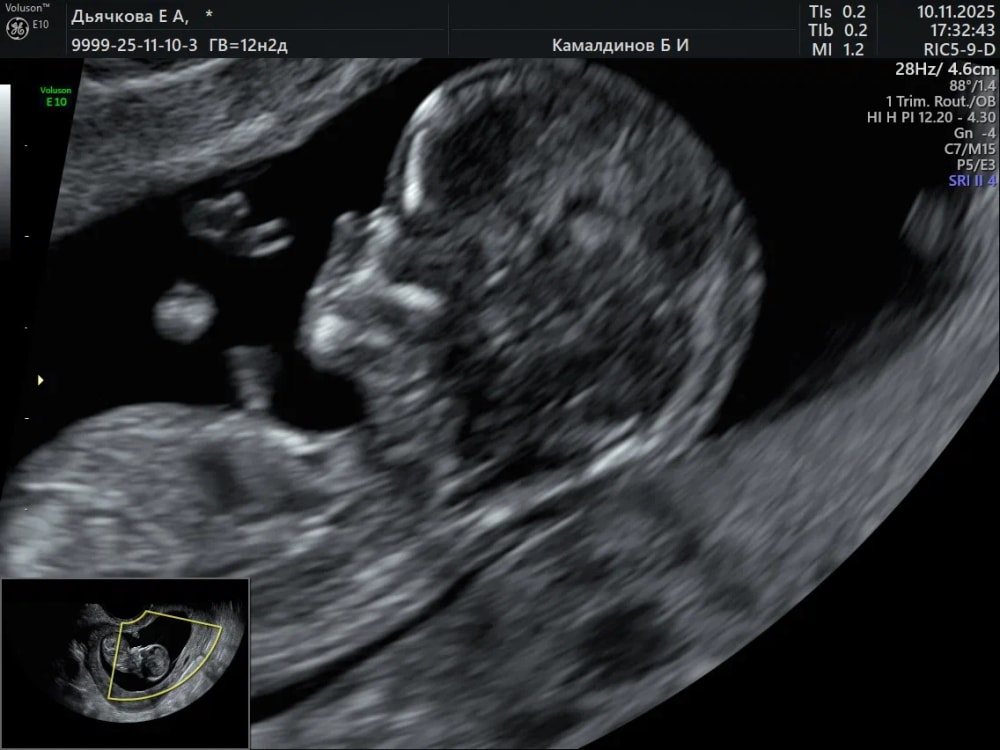

1 скрининг в мой день рождения)

Анализы, скринингиСказали все хорошо по УЗИ, ждем кровь и будет картина яснее. Малыш 5,3см🤍